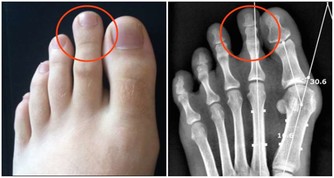

01.足三里

足三里是胃經合穴,所謂合穴是指全身經脈流注會合的穴位,對於全身氣血不和或陽氣虛衰,尤其是胃經氣血不和所致的胃痛、腹脹、腹瀉、便秘等胃腸道消化不良的病症,都可以通過按摩、刺激足三里來進行治療和調理。